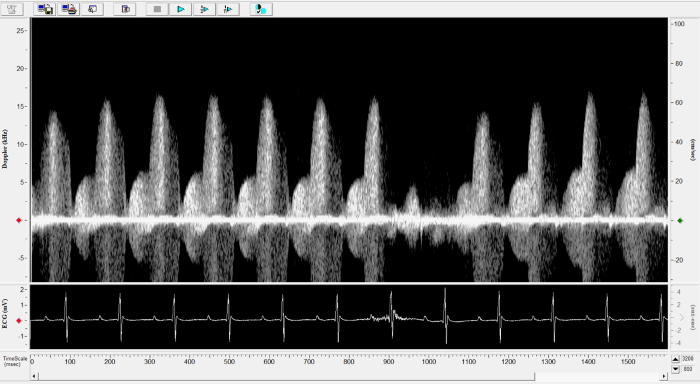

Mouse - Coronary Flow Reserve Imaging.

Mouse - Coronary Flow Reserve Imaging. Image Credit: Scintica Instrumentation Inc.